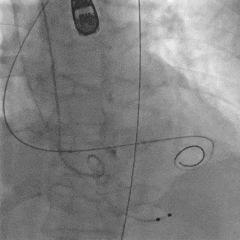

术中影像

瓣膜初始定位

第一次释放,瓣膜位置偏高,选择回收

第二次瓣膜释放